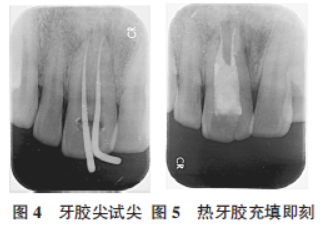

一周后复诊,主诉无特殊不适,检查见氧化锌丁香酚水门汀在位,叩痛(-),不松,牙龈仅见一瘘口,粟粒大小,无明显红肿,压痛(±)。去除氧化锌丁香酚水门汀及氢氧化钙,2.5%次氯酸钠冲洗根管,干燥,牙胶尖试尖(图4),Xray片示:试尖到位。行热牙胶+根充糊剂垂直加压充填,X-ray片示:恰充(图5)。